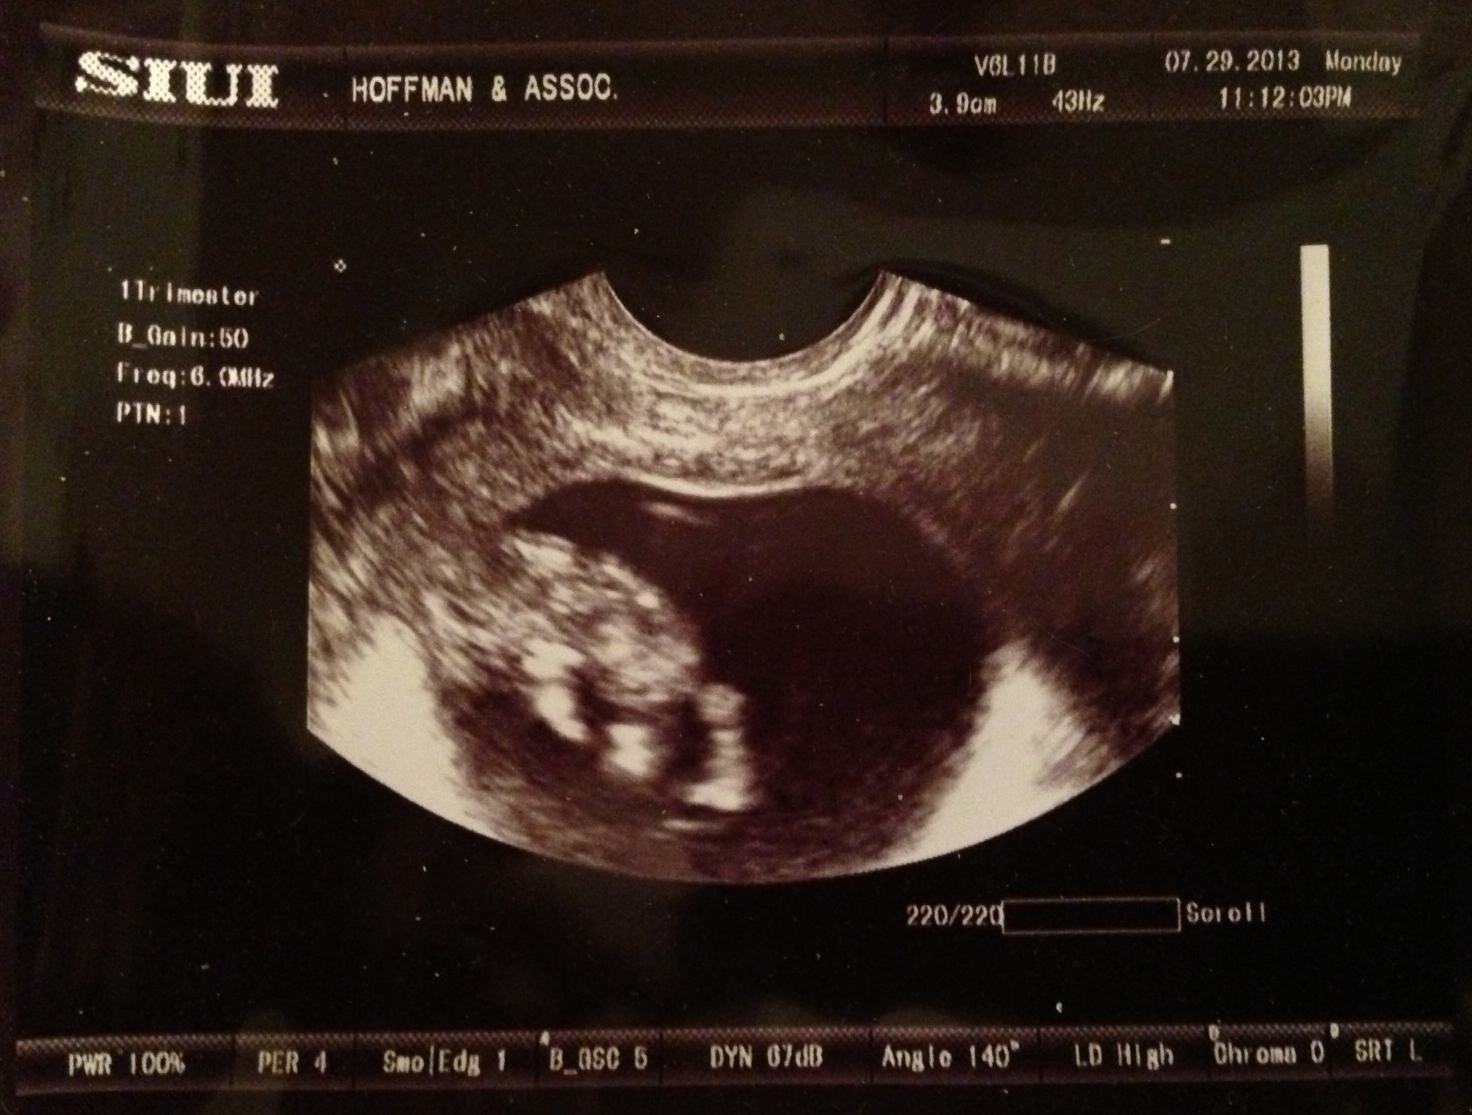

Me, Mom, Lauren and Katie had our monthly dinner and movie night. It was my turn to host. After a Thai, Japanese and Chinese meal, I decided to sneak our big surprise into the fortune cookies. I printed up some fake fortunes and slipped them into the cookies ahead of time. It took them a few minutes but eventually they put it all together.

Kristen’s fortune “Good things come in small bundles”

(Katie is the only one to hear this, she gives me a questioning face)Mom’s fortune “Be alert! You’re about to make a new lifelong friend”

(Katie is on to me. She smiles and keeps her mouth shut. Lauren starts squealing that Mom is going to get a puppy. Me and Katie are dying)Lauren’s fortune “Now is the time to congratulate a family member”

(Lauren drops her cookie and fortune on the ground and tells me Clemmie ate them. She did not thank goodness. After handing them to her, she starts asking everyone what they have to be congratulated on. Still no idea.)

Katie’s fortune “An important person will be pushed into your life come February”